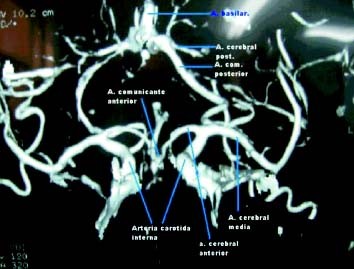

El Flujo sanguíneo cerebral es suplido en un 80% por las arterias carótidas y en un 20% por la circulación posterior. La circulación anterior y posterior, se anastomosan de tal forma en el polígono de Willis, que ante obstrucciones parciales o totales de algunas de las arterias de este polígono, se puede mantener un flujo parcial retrógrado por las otras arterias al área desprovista de circulación (foto 1). El infarto cerebral isquémico es secundario a ateroesclerosis de las grandes arterias intra o extracraneanas, aunque también de embolismo cardíaco y ateroesclerosis de pequeñas arterias. La enfermedad ateroesclerótica de la arteria carótida es la primera causa y la principal localización de las lesiones es la bifurcación carotidea (foto 2).